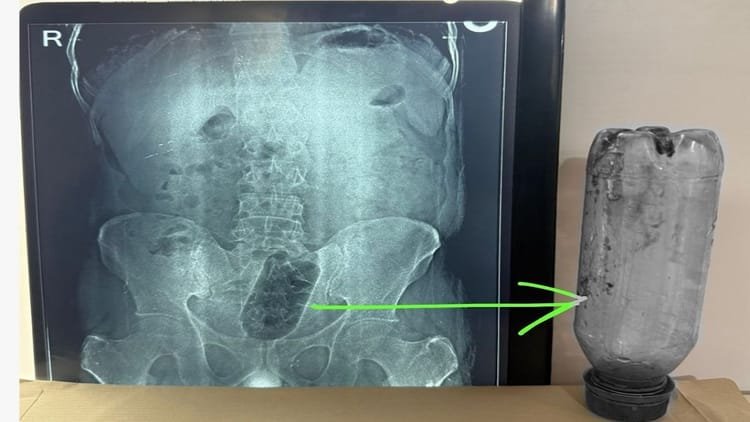

Bottle stuck in youth’s rectum: Endured unbearable pain for 36 hours, operation lasted 75 minutes; Know what the doctor said? – Bottle Lodged In Mans Rectum Surgery Brings Relief From Pain

The patient told that the bottle was stuck for 36 hours. After X-ray, the special team took out the bottle after an operation of about one and a quarter hour. The patient was discharged after wound healing and no problem in defecation.

Bottle stuck in young man’s rectum – Photo: Amar Ujala

After an operation at Navdeep Hospital in Saket Colony, Agra, UP, a one liter plastic bottle was taken out from the youth’s rectum. She was stuck for 36 hours. The patient got relief from pain after the operation. The patient has been discharged after his condition improved.